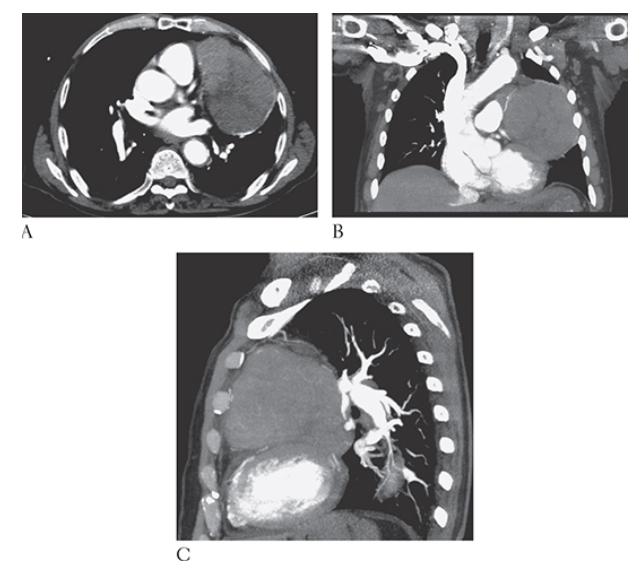

What is A

Thymoma. Posteroanterior (PA) and lateral

What is B

Thymoma. Posteroanterior (PA) chest radiographs show a large left anterior mediastinal mass projecting over the left lung.